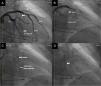

ProcedimientoEn concordancia con protocolo establecido en la institución, la paciente fue llevada a sala de hemodinámica y bajo sedación anestésica intravenosa se instaló un electrodo de marcapaso transitorio a través de punción yugular interna derecha. Se comprobó adecuada estimulación y captura y se dejó marcapaso a demanda con frecuencia de 60 lpm y salida de 6mV. Se hizo ecocardiograma transtorácico con equipo Vivid E 9 XDclear, al igual que cateterismo izquierdo previa preparación de regiones inguinales mediante asepsia y antisepsia en forma usual. Se colocaron campos en zona de punción femoral con anestesia local con xilocaína al 2% sin epinefrina; luego de la inserción bilateral de introductores en ambas arterias femorales mediante técnica de Judkins en arteria femoral derecha e izquierda, se pasó heparina 10.000 unidades intravenosa. Por vía femoral izquierda se introdujo catéter pig–tail 6F dejándolo en ápex del ventrículo izquierdo conectado a transductor de presiones. Por vía arterial femoral derecha se introdujo catéter guía Judkins izquierdo 6F. Se realizó angiografía selectiva de la coronaria izquierda; se localizó la primera rama septal. Por el catéter guía, se introdujo guía metálica de 0,014 pulgadas y 300cm de largo, posicionándola en arteria primera de la rama septal y a través de ella se pasó balón de angioplastia Apex-Push Over The Wire 1.5mm por 8mm, colocándose en tercio proximal de la primera septal. Se procedió a llenar balón a presión de 6 ATM dejándolo inflado a fin de ocluir la rama septal. Se retiró guía y se inyectó medio de contraste previamente hiperagitado, para realizar el contraste guiado por ecocardiograma transtorácico, delimitando la arteria septal donde se haría la ablación con alcohol (fig. 1). Con ayuda de este procedimiento se confirmó que la primera rama septal es la rama que da el flujo más significativo a la zona septal y es donde se debe hacer la ablación.

Ecocardiograma bidimensional que muestra la marcación del septum con medio de contraste hiperagitado. A) Imagen ecocardiográfica bidimensional que muestra el septum interventricular hipertrófico antes de pasar el medio de contraste. B) Inicio del paso del medio de contraste por la arteria primera septal comenzando a demarcar la zona septal de mayor irrigación. C) Inicio de la colocación del alcohol en la primera rama septal.

Mientras se mantenía inflado del balón a 6ATM se pasaron 1,5ml de alcohol (etanol al 98%) durante 5 minutos, después de los cuales se mantuvo inflado 5 minutos más y luego se lavaron los restos del alcohol en la arteria con solución salina. Se repitió angiografía por el catéter guía, observando oclusión completa de la primera rama septal (fig. 2).

A) Angiografía de la arteria coronaria izquierda; las flechas demarcan la rama primera septal. B) Se posiciona la guía 0,014” en la rama primera septal y sobre esta se pasa el balón de angioplastia 1,5 x 8mm. C) Infusión del medio de contraste hiperagitado en la arteria primera septal. D) Infusión de alcohol en la rama primera septal.